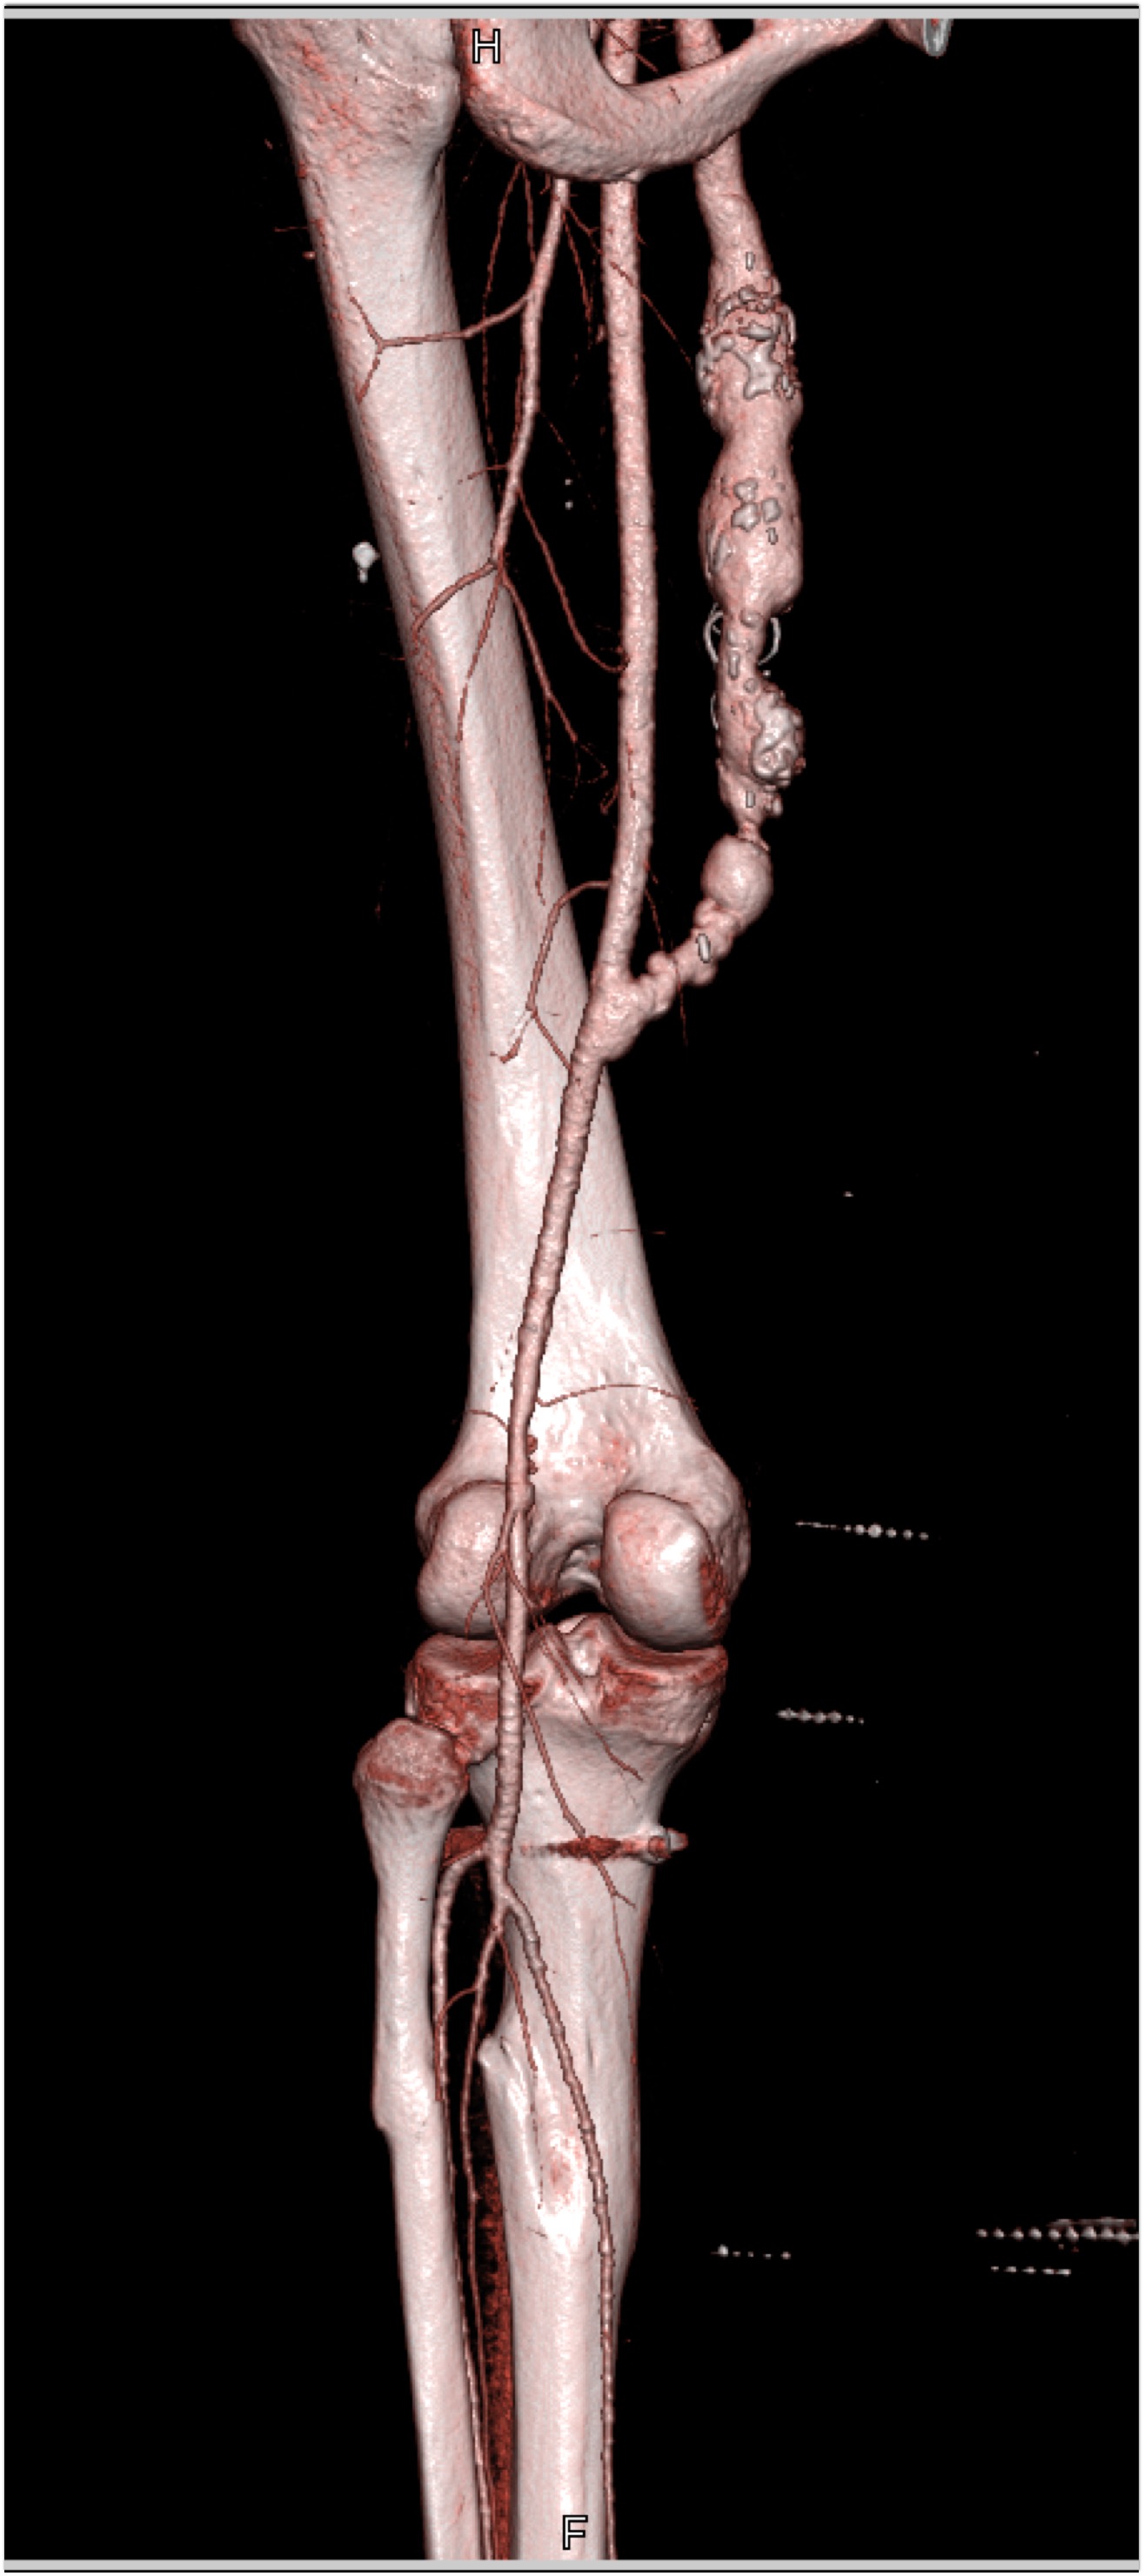

2) In this patient on dialysis for ESRD the best diagnosis is?

normal bypass graft

AV fistulae with aneurysms

vasculitis

infectious vascular disease